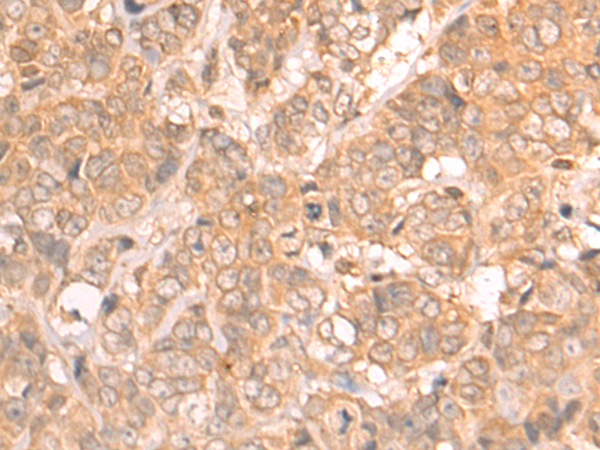

分类: 科研抗体货号: P07194别名: HER3; FERLK; LCCS2; VSCN1; ErbB-3; c-erbB3; erbB3-S; MDA-BF-1; c-erbB-3; p180-ErbB3; p45-sErbB3; p85-sErbB3应用: IHC反应种属: Human, Mouse, Rat